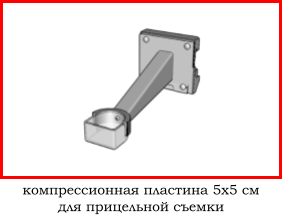

4.2 обычно отсутствует возможность прицельной съемки (специальная компрессионная пластина квадратной или округлой формы),

4.2 наличие принадлежностей для прицельной съемки,

В зависимости от высоты устройства достигается коэффициент геометрического увеличения объекта исследования 1.5х, 1.8х или 2.0х.

Метод прицельной маммографии с увеличением применяется для более детального исследования определенной области молочной железы. Он отличается высокой точностью диагностики. В отличие от обычной маммографии, которая предоставляет более общую информацию о состоянии молочных желез, прицельная маммография с увеличением позволяет получить точные данные о процессах, происходящих в тканях, благодаря методу компрессии конкретного участка.